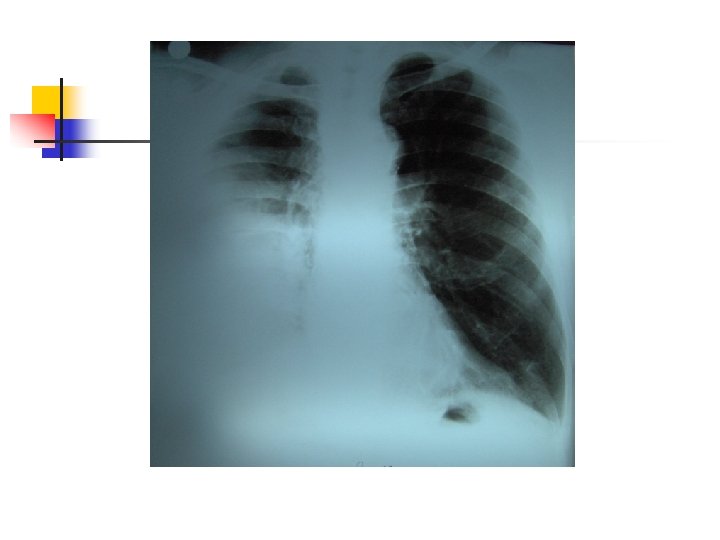

Aproximación diagnóstica: Radiología n n n 250 ml son necesarios para provocar alteraciones radiológicas. Primer signo: Borramiento del SCD Damoisseau. Desviación de estructuras. Derrame tabicado.